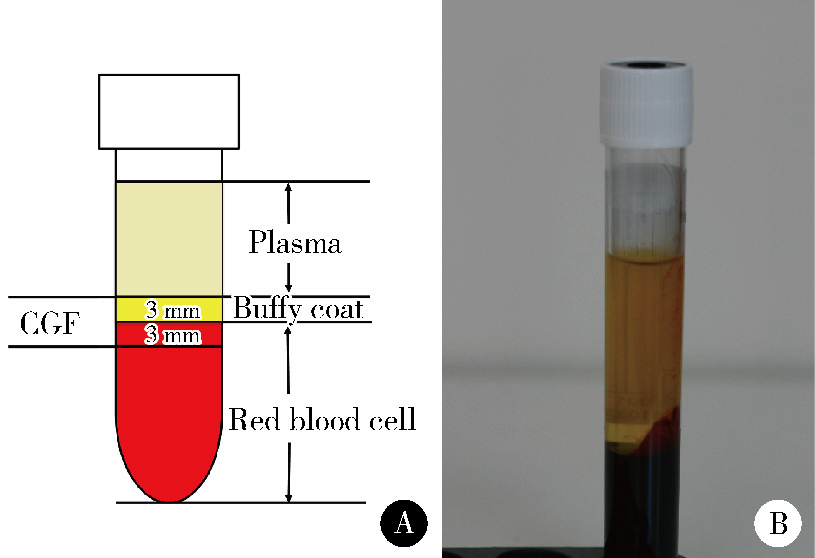

Effect of concentrated growth factors in guided tissue regeneration for the treatment of mandibular molar furcation lesions

| [5] | Xinying WANG, Xueyuan CHENG, Yong ZHANG, Fei LI, Jinyu DUAN, Jing QIAO. Therapeutic effect of concentrated growth factors combined with self-curing calcium phosphate cement on periodontal intrabony defects: Clinical and radiographic evaluation [J]. Journal of Peking University (Health Sciences), 2025, 57(1): 42-50. |

| [14] | Fei LI,Jing QIAO,Jin-yu DUAN,Yong ZHANG,Xiu-jing WANG. Effect of concentrated growth factors combined with guided tissue regeneration in treatment of classⅡ furcation involvements of mandibular molars [J]. Journal of Peking University (Health Sciences), 2020, 52(2): 346-352. |